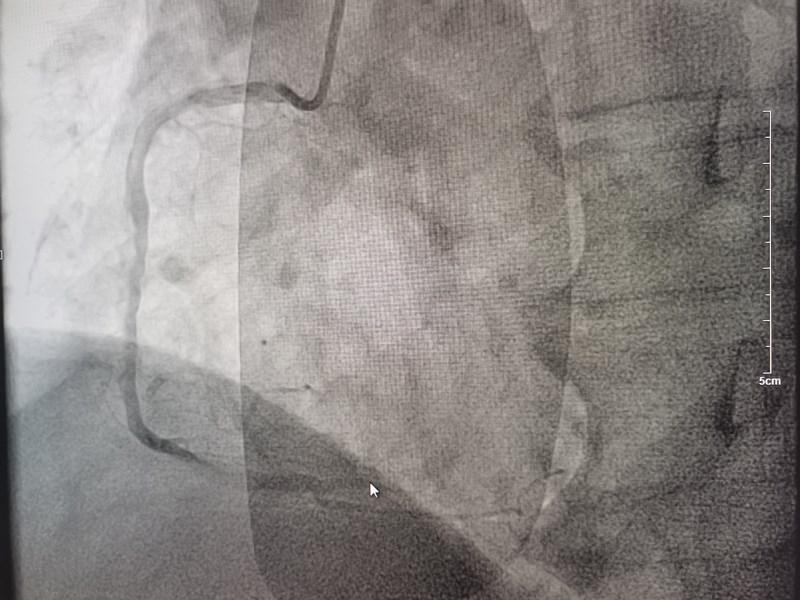

時間就是心肌,時間就是生命!一場生命的接力就此展開!心內(nèi)科團隊立即啟動胸痛綠色通道,電話通知導(dǎo)管室安排手術(shù)人員到位。董學(xué)濱副主任、汪韶君副主任醫(yī)師,以及導(dǎo)管室工作人員有條不紊地備好主動脈球囊反搏機、呼吸機等急診冠脈造影術(shù)前的各項準備工作,以及術(shù)中可能出現(xiàn)的各種突發(fā)狀況的應(yīng)急預(yù)案。23:42分,造影手術(shù)正式開始,術(shù)中顯示裴某巨大的右冠狀動脈全程彌漫性病變,PLA近端完全閉塞。此時裴某生命體征極不穩(wěn)定,表情淡漠血壓低,隨時可能出現(xiàn)心臟驟停!治療承受著巨大的壓力和風(fēng)險,心內(nèi)科團隊迎難而上,迅速將導(dǎo)絲通過閉塞血管,球囊擴張、打通閉塞的血管、植入支架,整個手術(shù)過程嫻熟、精準。隨著阻塞血管血流的恢復(fù),裴某慢慢睜開了眼睛,神志恢復(fù),胸痛癥狀消失,生命體征逐漸趨于平穩(wěn)。整個手術(shù)僅用時一小時。

術(shù)前

術(shù)后